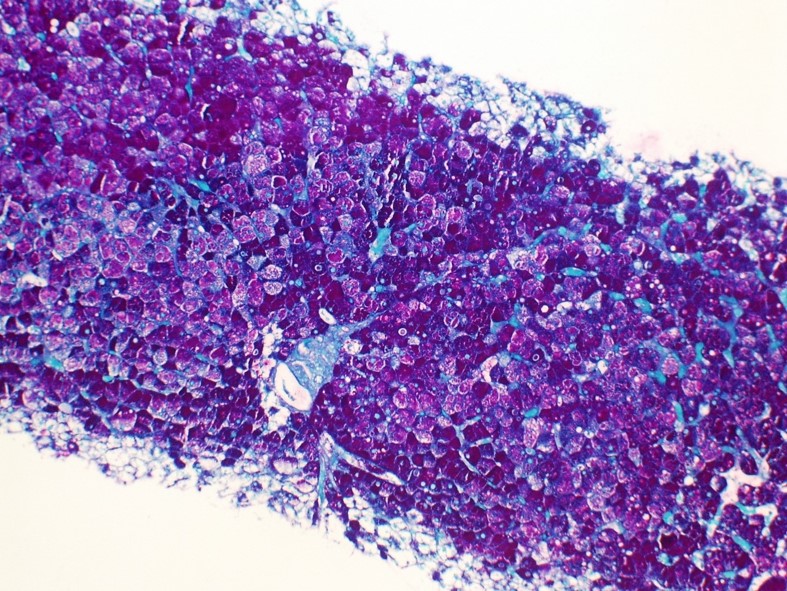

A 21-year-old man presented with a clinical history of cryptogenic cirrhosis. Grossly, the explant liver was noted to be very firm. Sectioning revealed parenchymal color varying from dark red to tan white with dilated ducts and apparent stones. No discrete lesion was identified. Histologic examination revealed numerous partially involuted hepatic regenerative nodules often surrounded by swaths of gland-like tissue, the lumens of some showing calcifications and occasional red blood cells. Cytologically, no increased mitoses or necrosis were noted. Immunostains showed these areas to be positive for CD34, CD31, and negative for CDX2 and CA 19.9.

Answer: B.) t(1;3)(p36.3;q25), CAMTA1- WWTR1